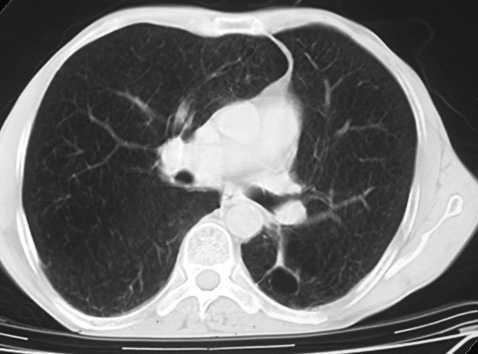

El primer caso era un varón de 57 años con antecedentes de hábito tabáquico y relación laboral con moldes de arena. Se le practicó un trasplante bipulmonar secuencial por un cuadro de silicosis en fase terminal. En la pieza quirúrgica se confirmó el diagnóstico de silicoantracosis, acompañado de abundantes áreas de enfisema bulloso pulmonar. Presentaba en el pulmón derecho un adenocarcinoma broncogénico moderadamente diferenciado, de 1,8 cm de diámetro máximo, en situación hiliar y muy próximo al bronquio principal, que afectaba por contigüidad a una adenopatía de dicha región y que fue clasificado como T1N1M0 (estadio IIa)5 (fig. 1). Transcurridos 6 meses desde el trasplante, se detectó la presencia de múltiples metástasis óseas en la columna vertebral y, 3 meses después, en el lóbulo izquierdo hepático. Se valoró al paciente desde el punto de vista de su enfermedad oncológica y se consideró únicamente su tratamiento paliativo con radioterapia por un cuadro de dolor persistente. Falleció a los 16 meses del trasplante por progresión de la enfermedad tumoral.

Fig. 1. Caso 1: adenocarcinoma broncogénico.